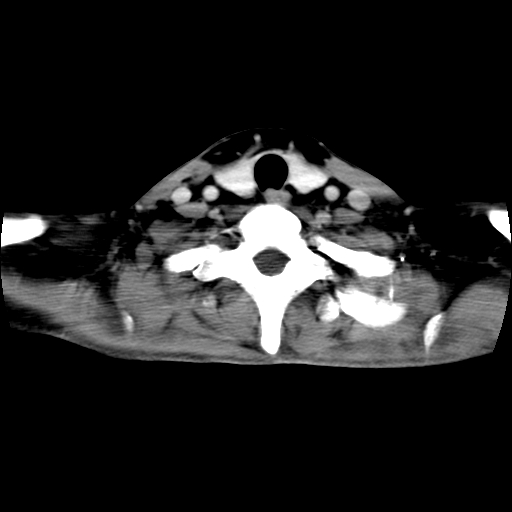

标题: CT24019:男,45岁,发现颈部肿物5个月。 [打印本页]

男,45岁,发现颈部肿物5个月,彩超示:双侧颈部及下颌部软组织增厚。

考虑双侧颈项部良性对称性脂肪增多症。

双侧颈项部脂肪沉积